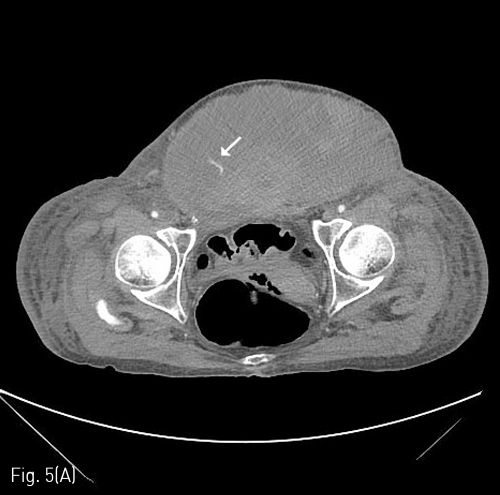

Fig 5A

(A) 11 days later, the size of the abdominal wall hematoma is more increased with inferior extension (about 34 x 18cm), and another active bleeding is noted at the lower abdominal wall. The bleeding focus was from the left inferior epigastric arterial branch on angiography, and treated with gelfoam embolization(white arrow).

Fig 5B

(B) Pseudoaneurysm formation is noted at previous angiographic catheterization site of the left common femoral artery (black arrow).